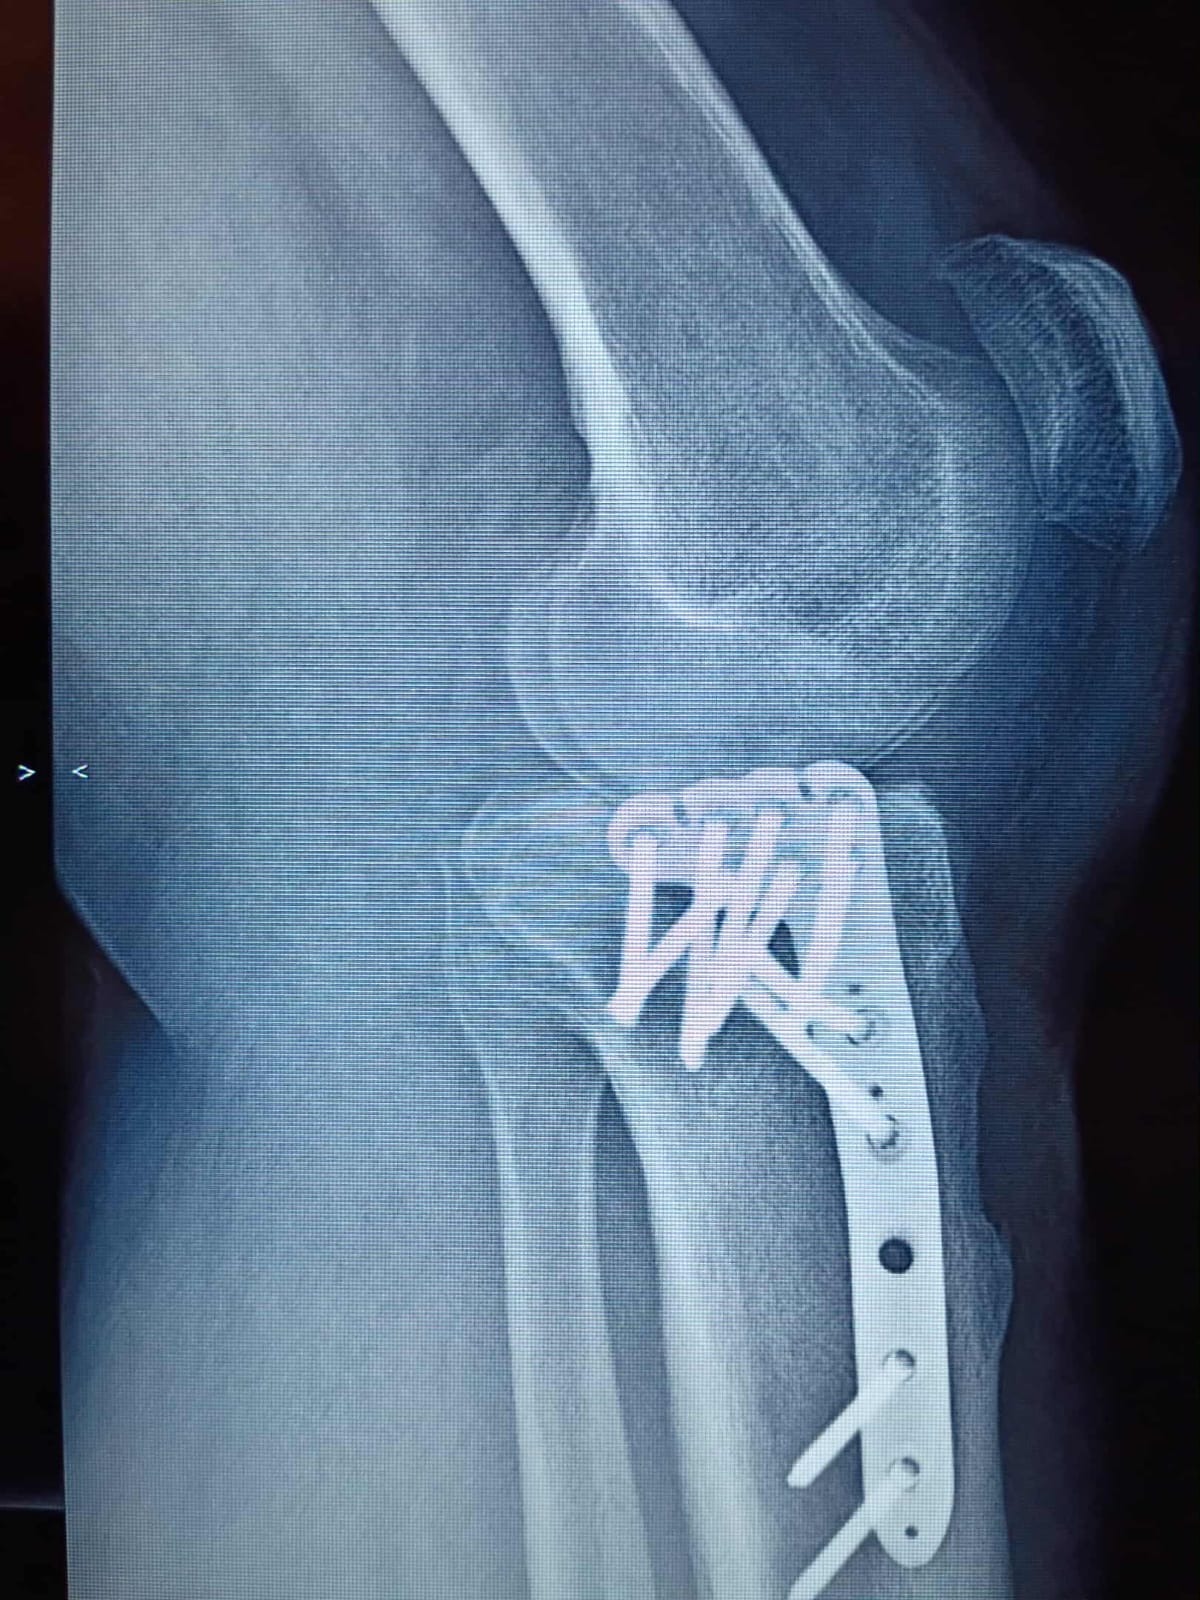

On September 15, 2024, I suffered a serious injury and broke my tibia. Since that day, my life has been turned upside down. I’ve been unable to work and do the things I normally take pride in—providing for myself and my family.

I’ve done my best to stay strong and push through this difficult time, but the reality is that recovery has been longer and more challenging than I ever expected. Now, I am facing surgery scheduled for April 23, and with it comes medical expenses that I am simply not able to handle on my own.